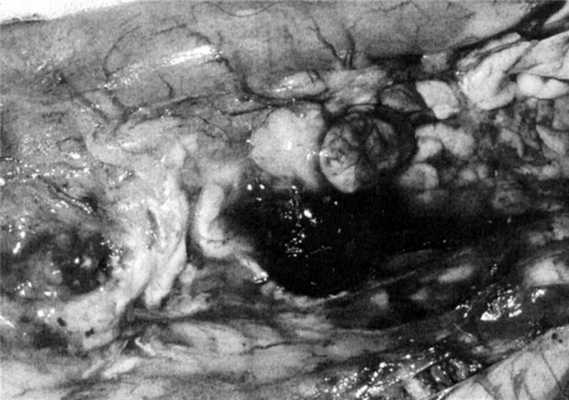

Экспериментально установлено, что при выбранной модели у всех животных возникал острый панкреатит с соответствующими макро- и микроскопическими проявлениями (рис. 1), Рисунок 1. Макроскопическая картина поджелудочной железы с прилежащими к ней тканями на 3-и сутки развития острого панкреатита. причем в 4 случаях происходило прогрессирование панкреатита, развивался тотальный панкреонекроз. Одним из клинико-лабораторных признаков острого панкреатита явилось повышение (на 145-297,9%) уровня α-амилазной активности и синдром эндогенной интоксикации, прогрессирующий несмотря на применение инфузионной терапии, что проявлялось существенным повышением в плазме крови уровня гидрофильных и гидрофобных токсичных продуктов (индекс токсичности плазмы крови превышал норму на 60,0-290,2%; р<0,05).